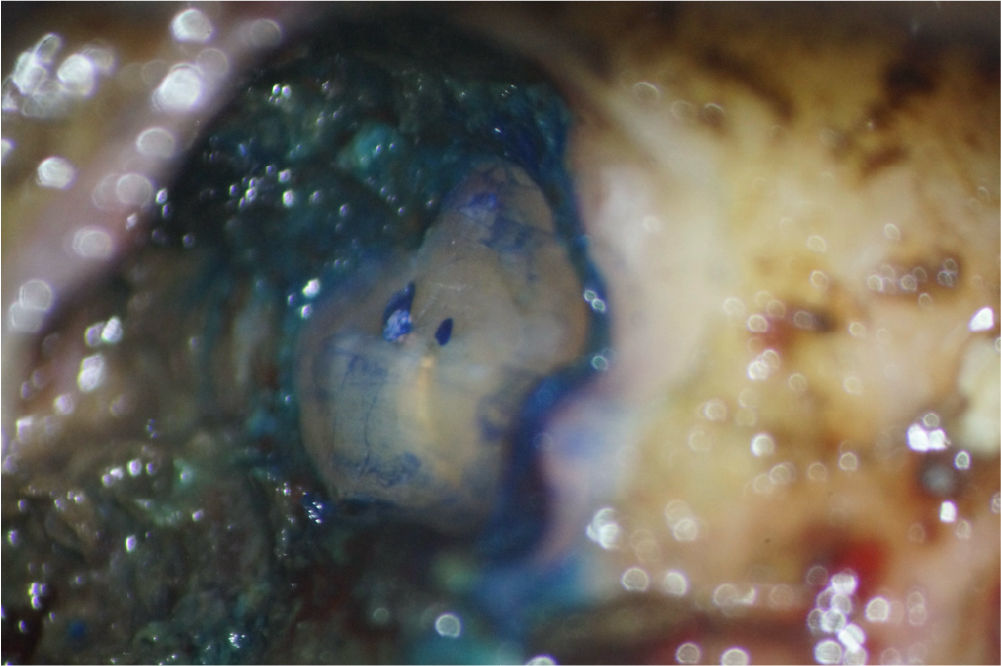

根管治療の症例

近心根切断面

遠心根切断面

上記の写真は、歯根端切除後の切断面を顕微鏡を用いて精査している写真です。 歯内療法の専門医が外科的歯内療法(歯根端切除)を行い、術後の経過で骨の回復が確認でき、良好な治癒につながりました。